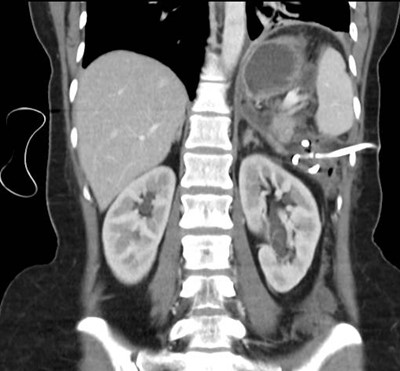

Caso 3

Mujer de 36 años que ingresa a Hospital Sanatorio Franchin el 11 de octubre de 2023 de forma programada para realización de duodeno pancreatectomía cefálica por tumor de cabeza de páncreas en estudio. Refiere hallazgo de lesión en forma incidental durante estudio de control hace dos meses por presentar antecedentes familiares (neoplasia endocrina múltiple). Se interna para manejo quirúrgico. Estudios de tomografía revelan formación nodular localizada en cabeza y cuerpo pancreático de paredes gruesas que mide 24 x 28 mm, que en resonancia se muestra hiperintensa en T2 y realce periférico luego de la administración de contraste endovenoso. Presenta restricción en la difusión con caída de la señal ADC, por lo que se vincula con una lesión de alta celularidad.

Laboratorios clínicos: Hto: 42 HB: 14.1 GB: 4200 Plaq: 231mil Glu: 90 Péptido C: 3.5 TGO: 17 TGP: 28 BT: 0.75 Fal: 179 Glucemia 109 TP: 100% KPTT: 36 Prots tots: 6.5 AlB 4.43.